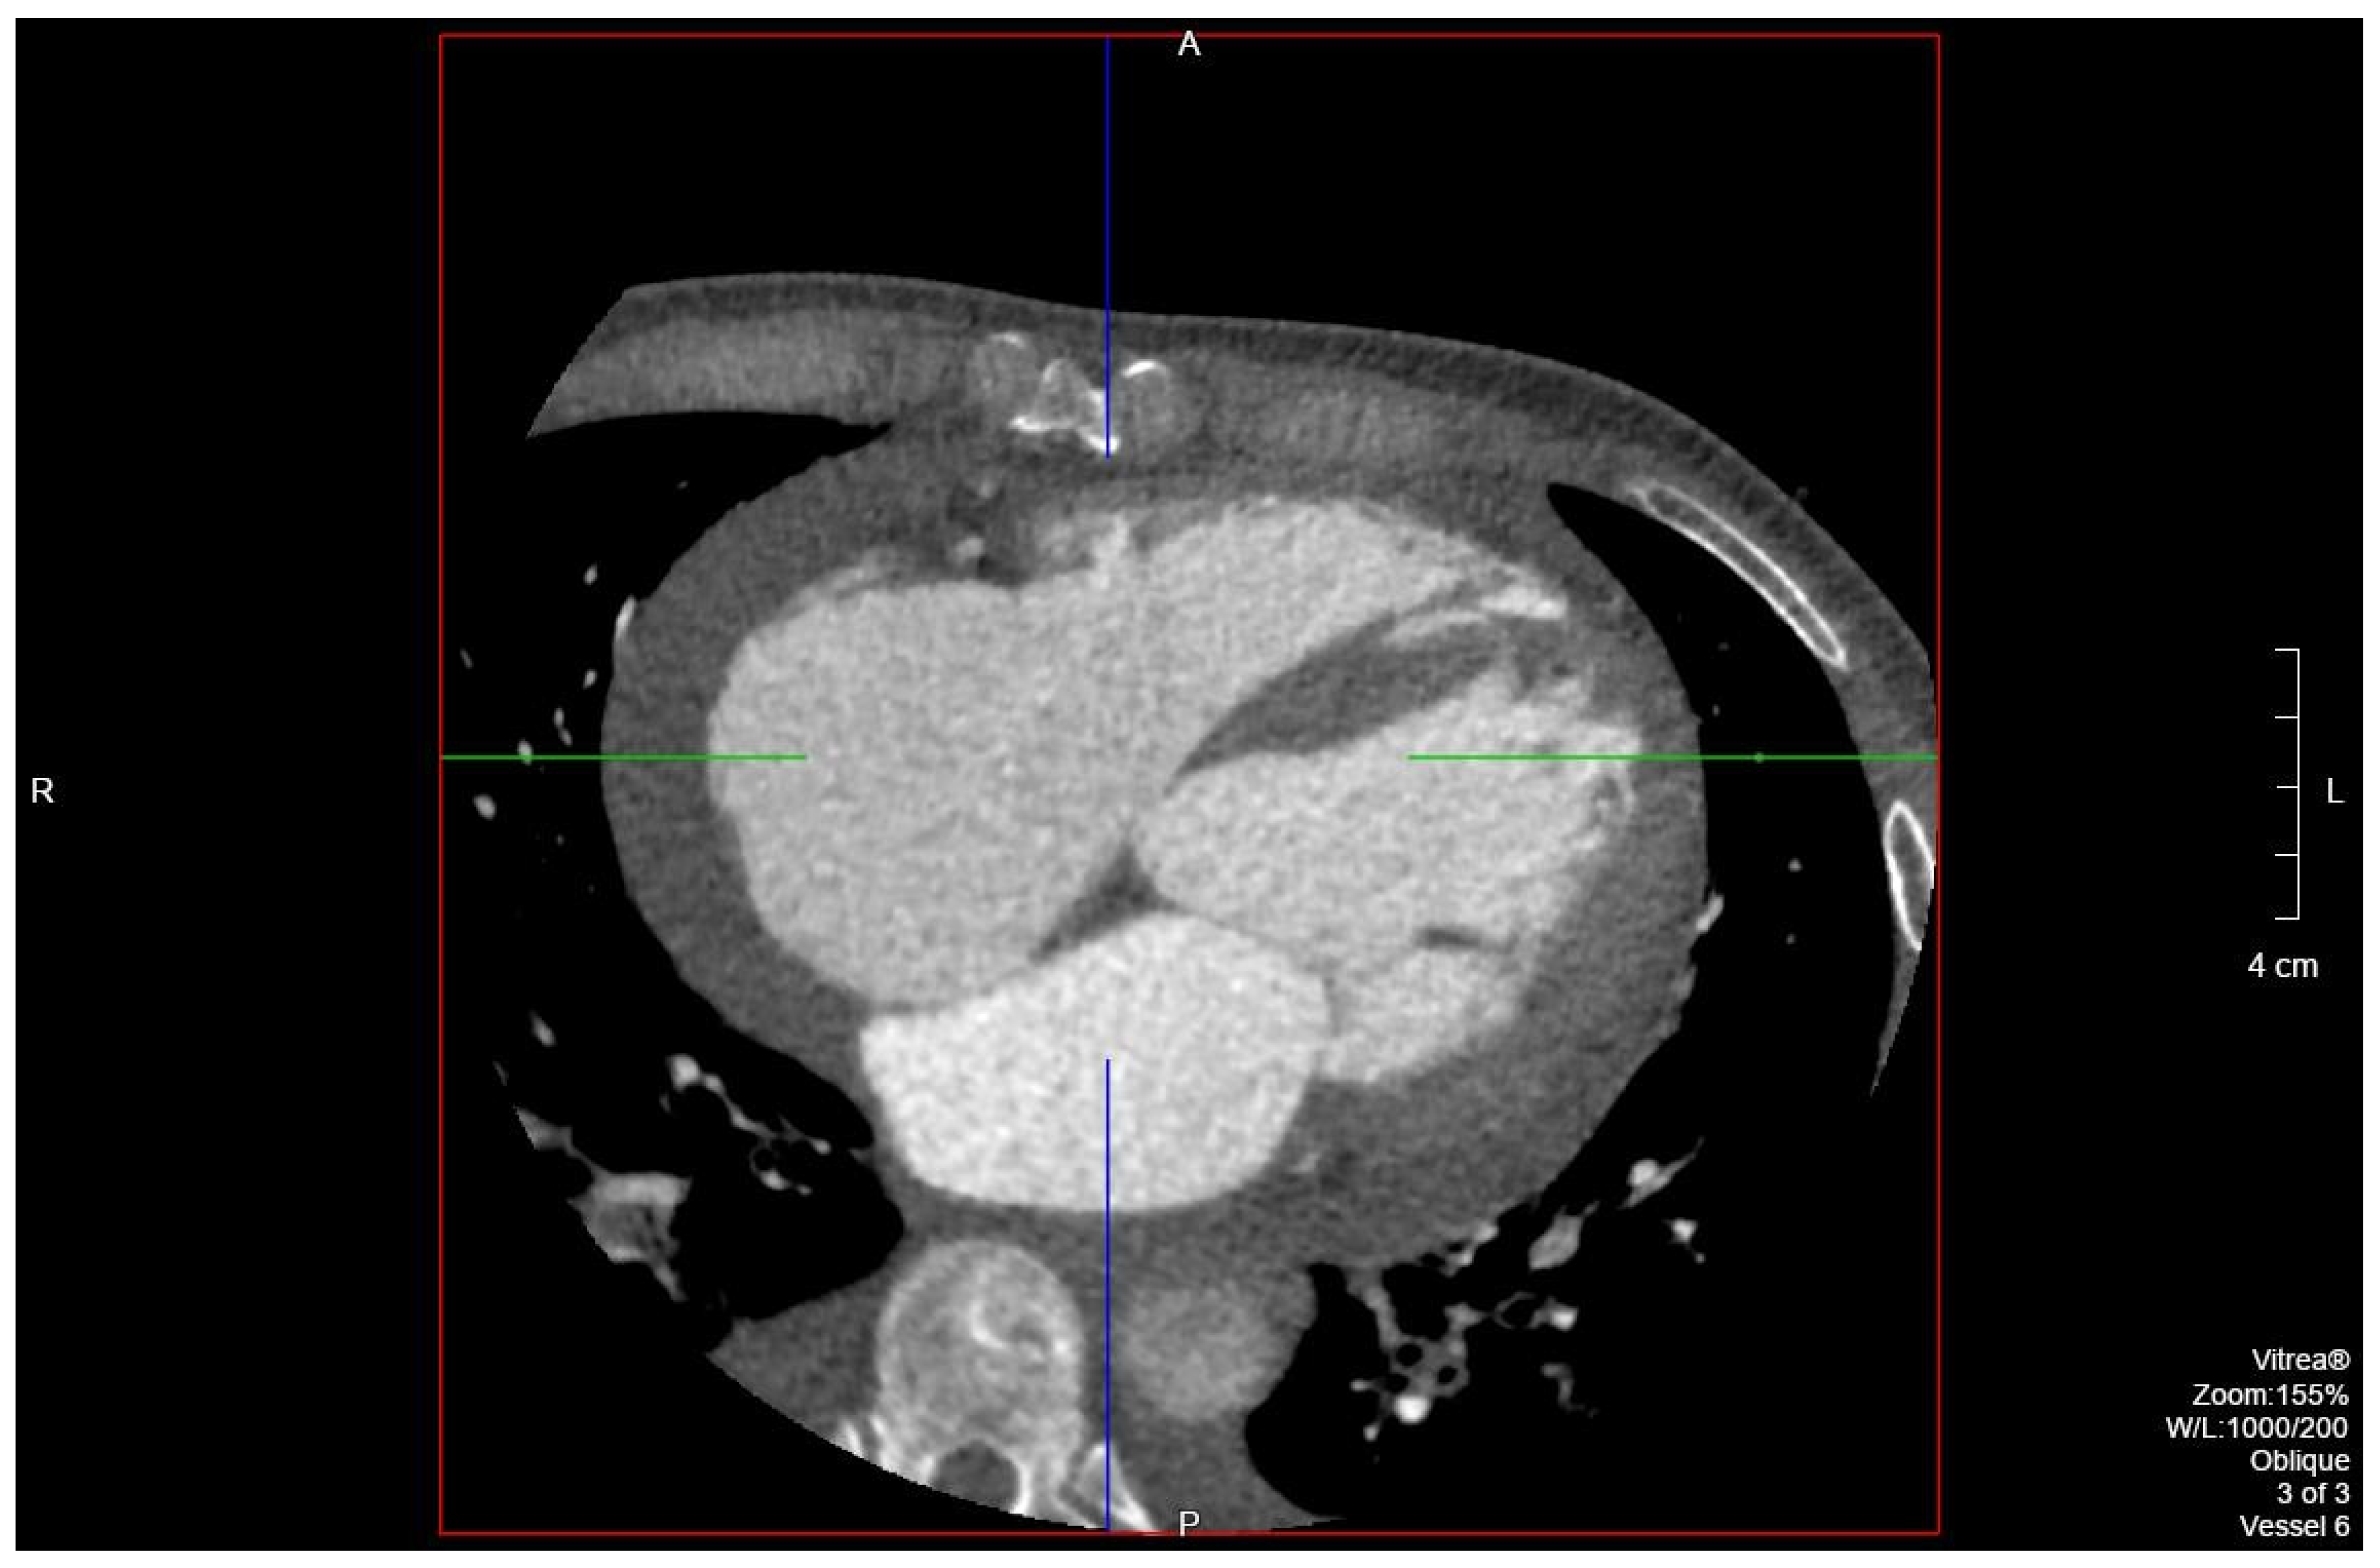

The patient’s EKG (Figure 1) on admission demonstrated a left bundle branch block pattern not previously documented in the patient’s medical history. Additionally, chest radiography (Figure 2) and computed tomography (Figure 3) on admission demonstrated cardiomegaly. Transthoracic echocardiography was technically difficult but demonstrated severe left ventricular systolic dysfunction with an ejection fraction of <15%. Initial brain natriuretic peptide (BNP) on admission was 981 pg/mL. The patient was recommended to start on 25 mg metoprolol succinate, 81 mg aspirin, 5 mg Lisinopril, and 40 mg atorvastatin. Metoprolol and Lisinopril were started initially as therapy for newly diagnosed DCM whereas aspirin and atorvastatin were started before coronary artery disease was ruled out with cardiac CT angiography (Figure 4 and Figure 5). The patient developed electrolyte abnormalities after the first day of treatment, including hypomagnesemia and hyperkalemia, likely secondary to longstanding untreated fluid overload due to heart failure. In response to this and the noted acute kidney injury, Lisinopril was discontinued. Additionally, the patient’s ALT and AST levels rose dramatically. Gastroenterology evaluation was obtained due to elevated liver function tests with a differential diagnosis of shock liver vs. Budd Chiari syndrome; therefore, N-Acetyl cysteine was prophylactically used and improved liver function over the subsequent week and atorvastatin was discontinued. The patient was continued on heart failure management. A repeat echocardiogram showed an improved ejection fraction of 25% with left ventricular dilation (left ventricular internal dimension in diastole 5.65 cm; left ventricular internal dimension in systole 4.95 cm; relative wall thickness 0.34; left ventricular mass 218.2 g; left ventricular mass index 131.8 g/m2) and no left ventricular thrombus noted. Additionally, mildly reduced right ventricular systolic function was noted.

Figure 4. Segment of cardiac CT angiography demonstrating cardiomegaly and no coronary artery disease.

Figure 5. Segment of cardiac CT angiography demonstrating cardiomegaly and no coronary artery disease.